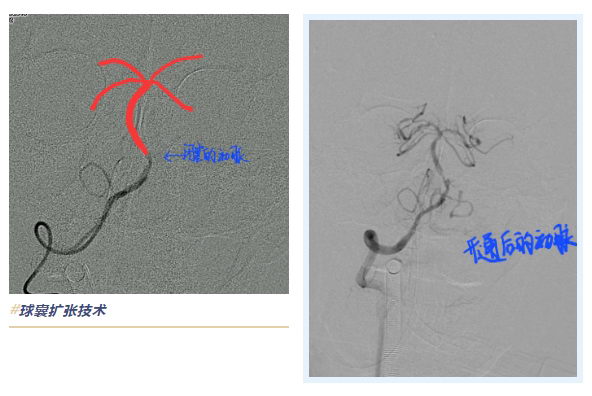

在重症医学科、麻醉科等多学科团队的紧密配合下,患者接受全脑动脉造影检查,确诊为基底动脉闭塞。神经血管介入科主任王振兴果断采用“支架取栓”技术,快速打通闭塞的基底动脉,并运用“球囊扩张技术”成功完成血管成形。术后,患者转入重症医学科观察。48小时后,患者顺利拔除气管插管,自主呼吸恢复。经过14天的精心治疗与护理,患者最终康复出院。